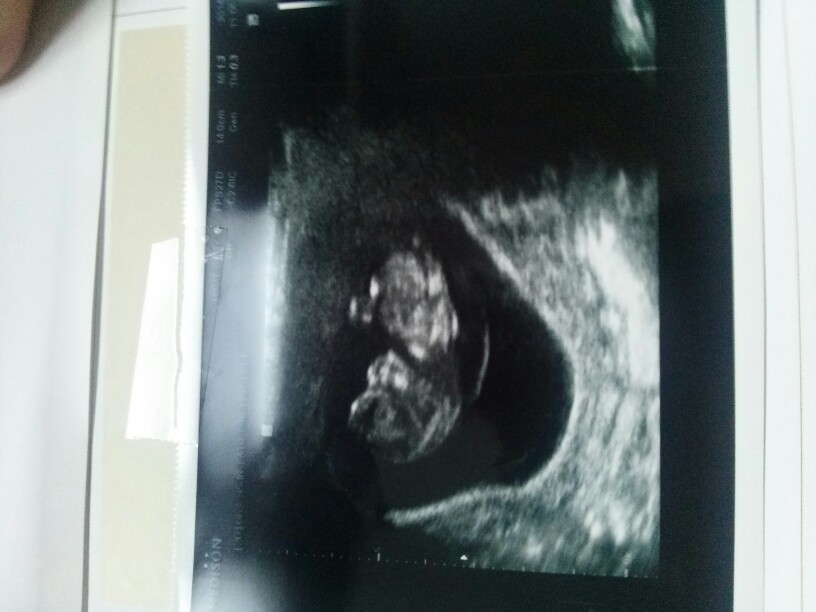

오늘 산부인과 정기검진이어서 막둥이 보고왔네요 ㅎㅎ 이젠 제법 사람같아요 ㅎㅎ

ㅎㅎ 오늘 보니 짝짝꿍 놀이하고 잘놀더라구요 ㅎㅎ

이런거 보면 맘이 어떨까요 ㅎ 아무튼 잘자라고 잇다니 좋아요